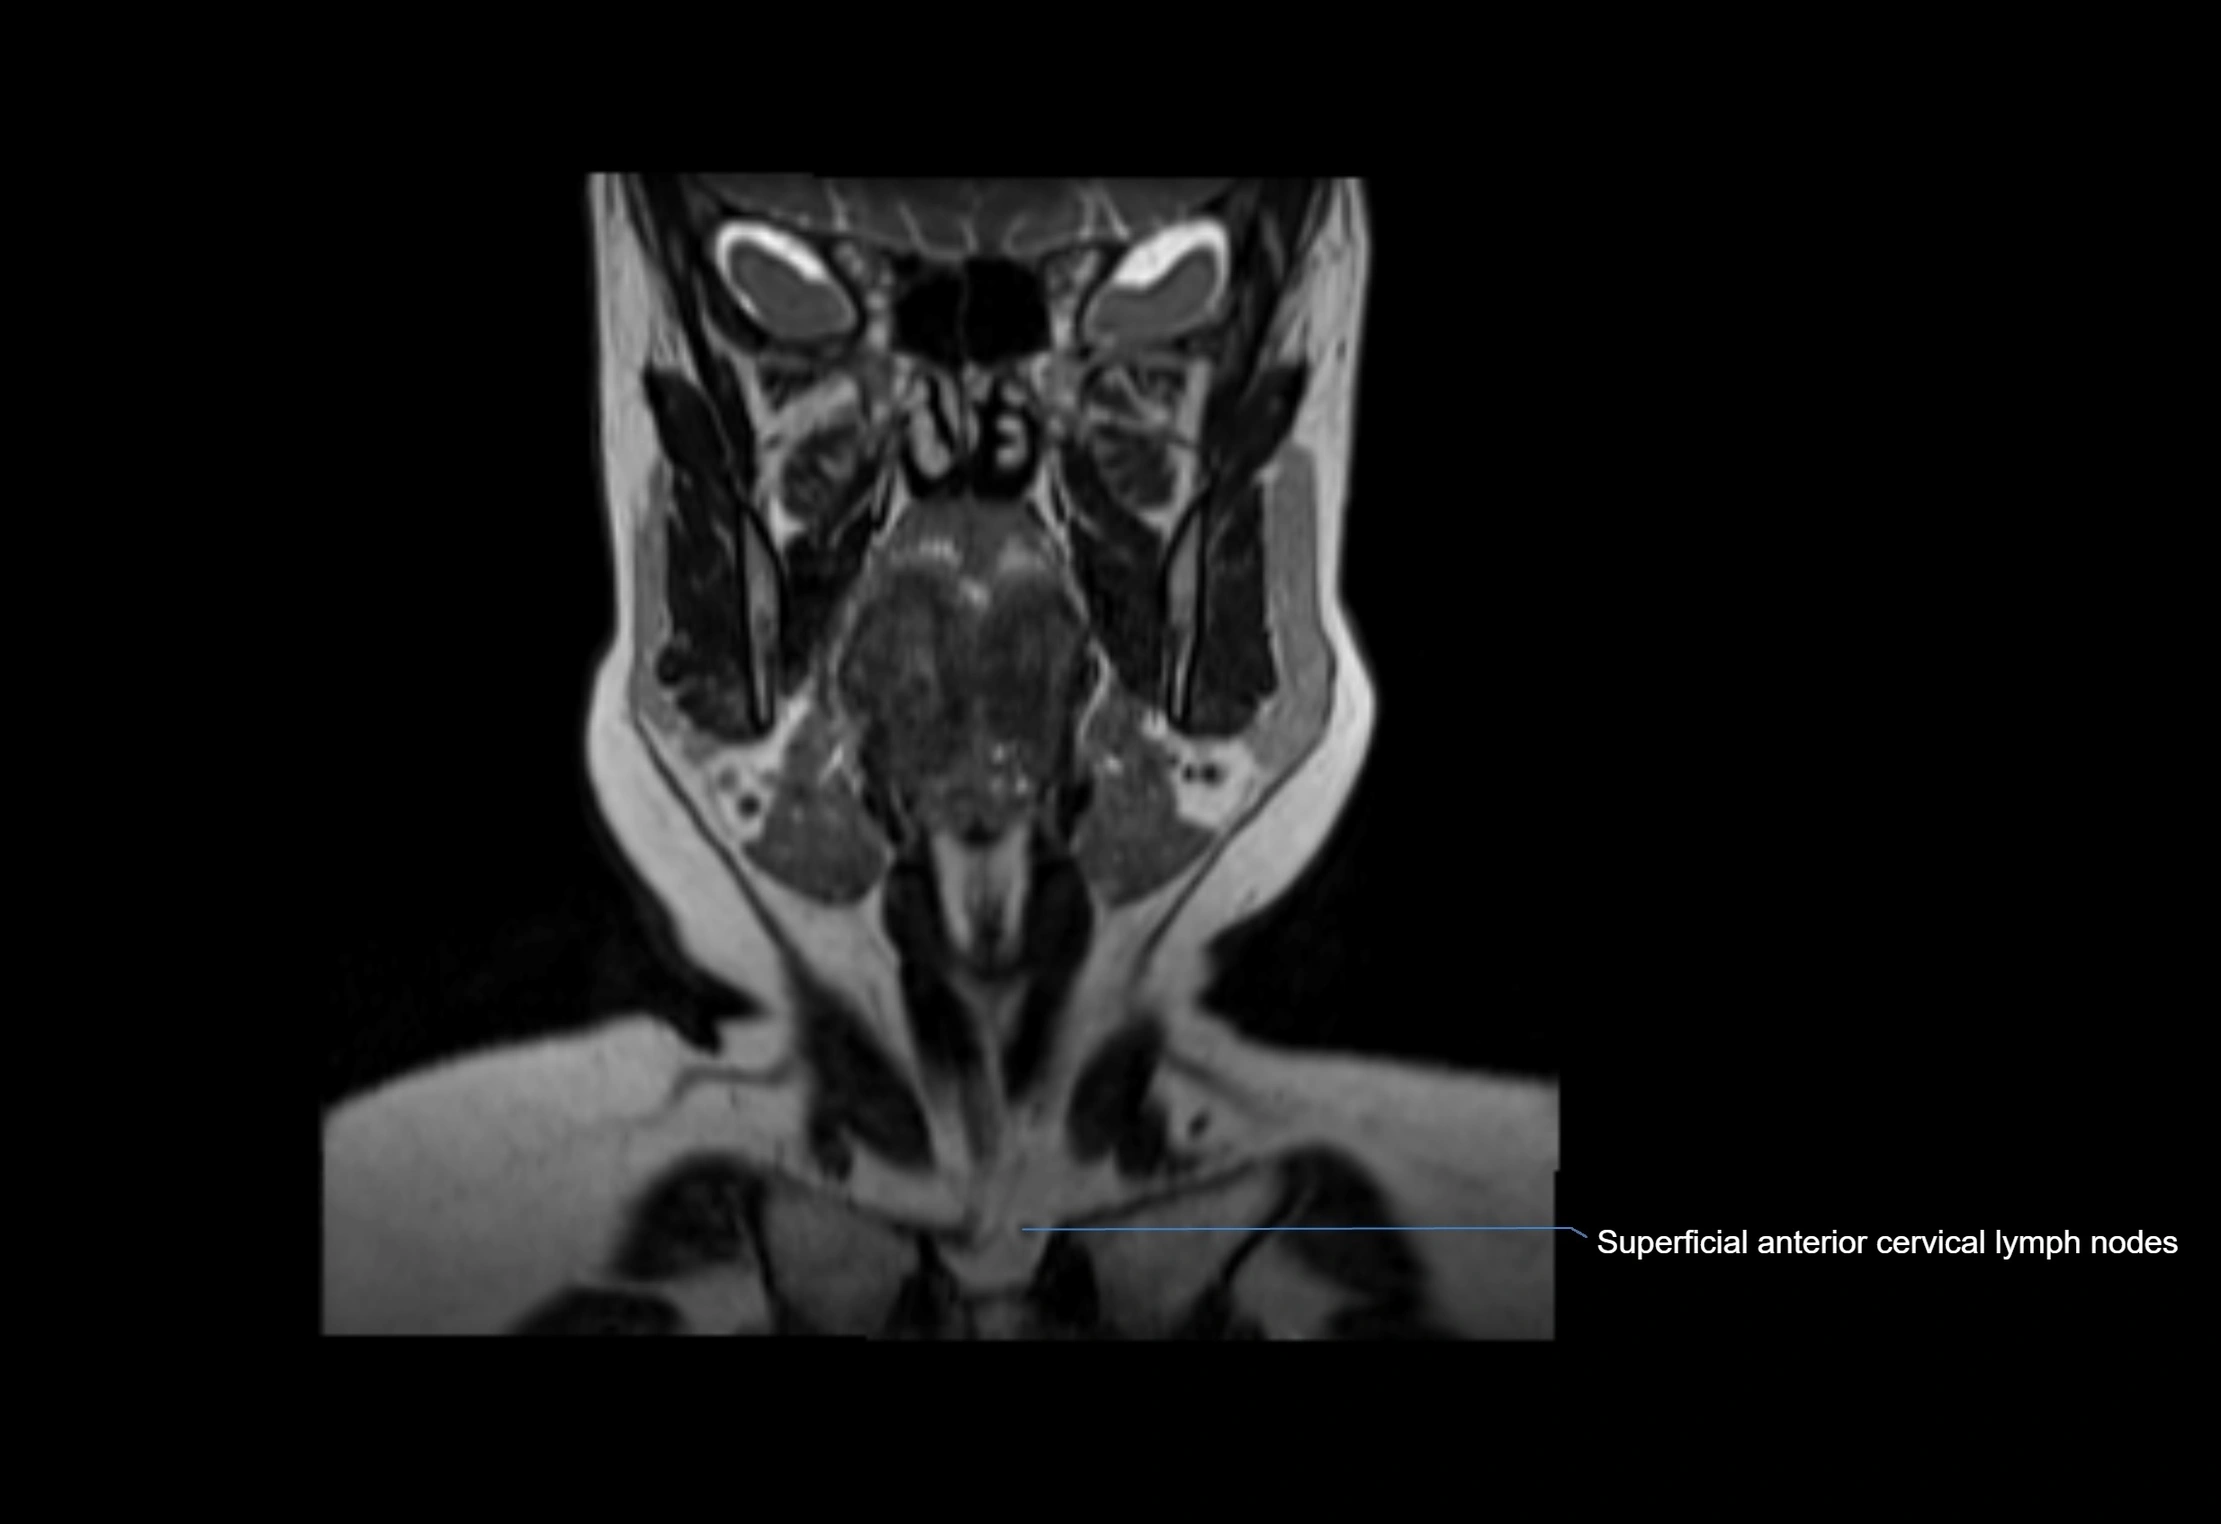

MRI images

image